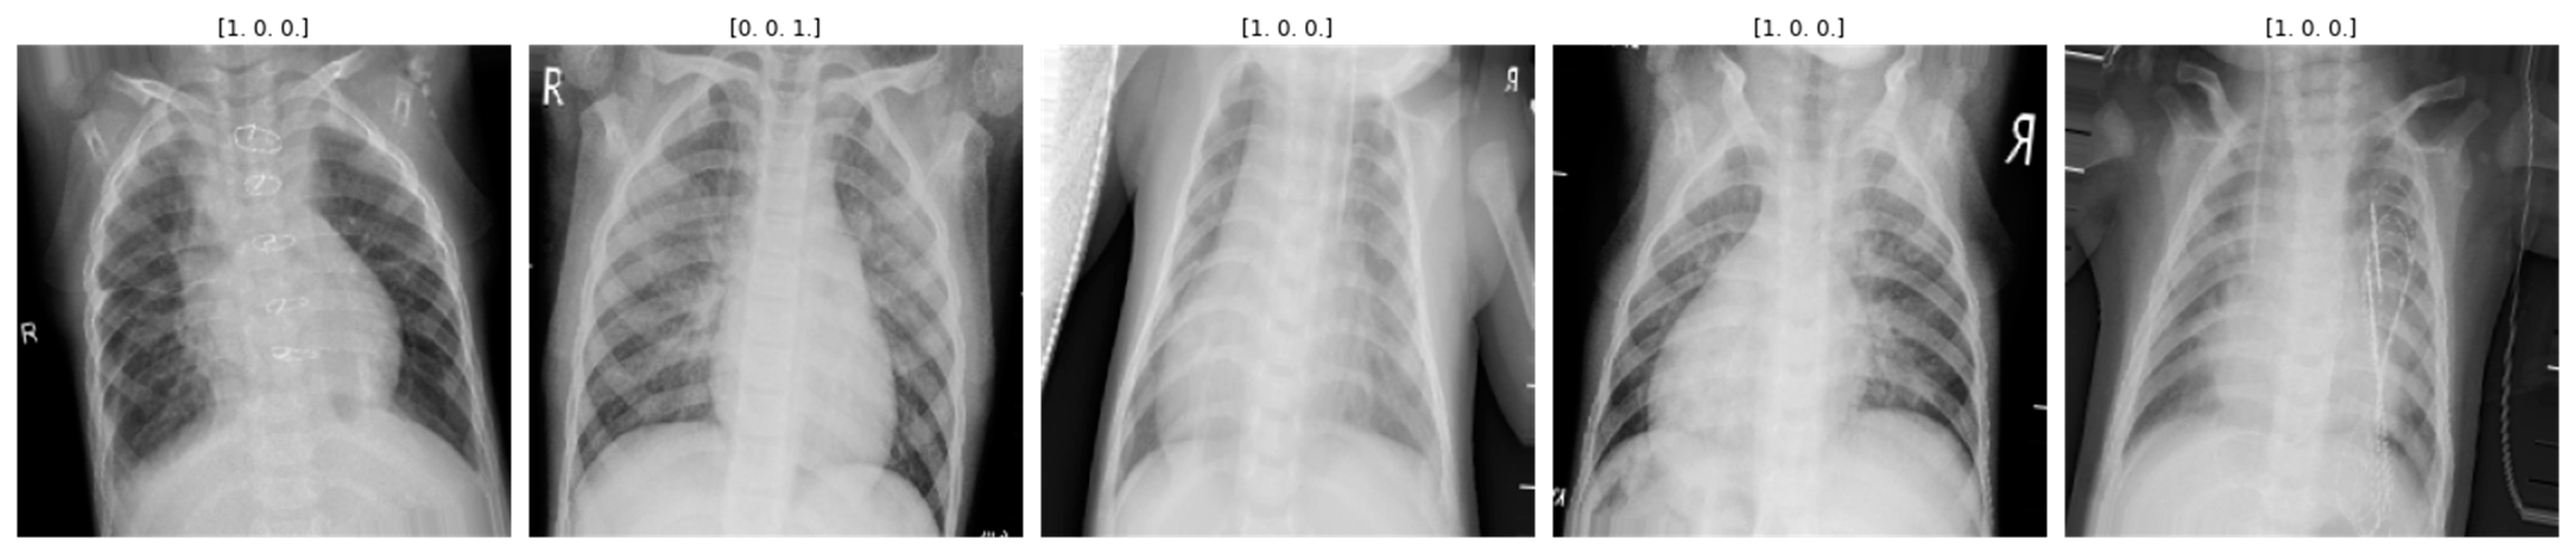

3.2.2. Data Augmentation to Control Class Imbalance

| Step 2: | Class Balance = Augmentation (preprocessed) |

| Category | Images | Data Augmentation |

|---|---|---|

| Normal | 375 | 12,000 |

| Pneumonia | 345 | 12,000 |

| COVID-19 | 375 | 12,000 |

| Lung Opacity | 400 | 12,000 |

| Total | 1495 | 48,000 |